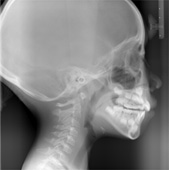

2.検査

検査では問診表をご記入頂くほか、以下の様々な項目を検査します。

また、ブラッシング指導やフッ化物洗口などの説明もいたします。

CTセファロ撮影、顔貌写真、鼻腔通気度、顎関節・頚部リンパ節の触診、口腔内写真、歯列模型の印象採得、舌小帯、頬の圧痕、身長、体重

3.診断

資料にまとめた検査結果を解説しながら、治療方法や期間、矯正装置、治療のゴールを説明していきます。

定期検査:3ヵ月に一度定期検査をします。

また、半年ごとに口腔内の撮影、1年ごとに姿勢と顔貌写真、鼻腔通気度、オルソ、セファロ撮影をします。

※CTは必要に応じて撮影します。